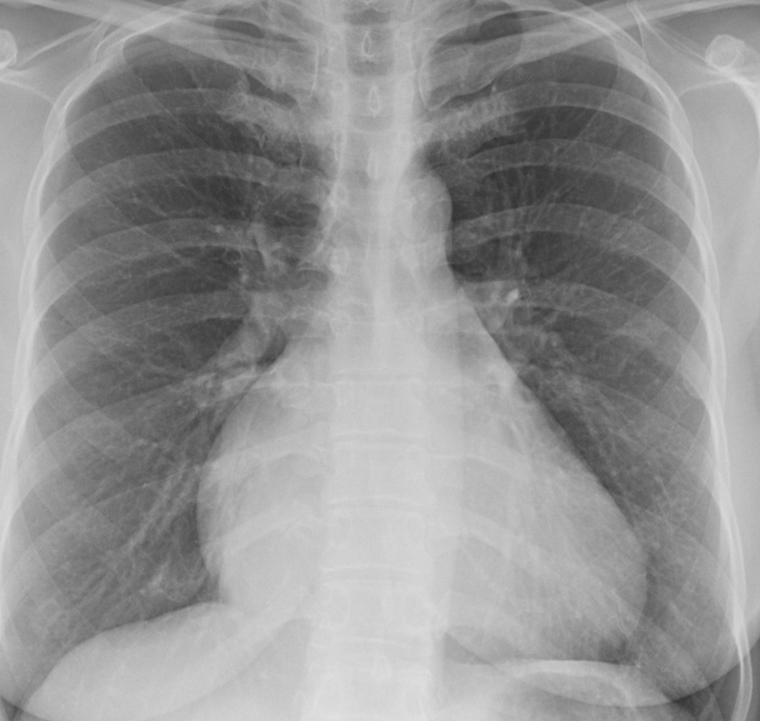

Tricuspid insufficiency PA

Date: 07/27/2013